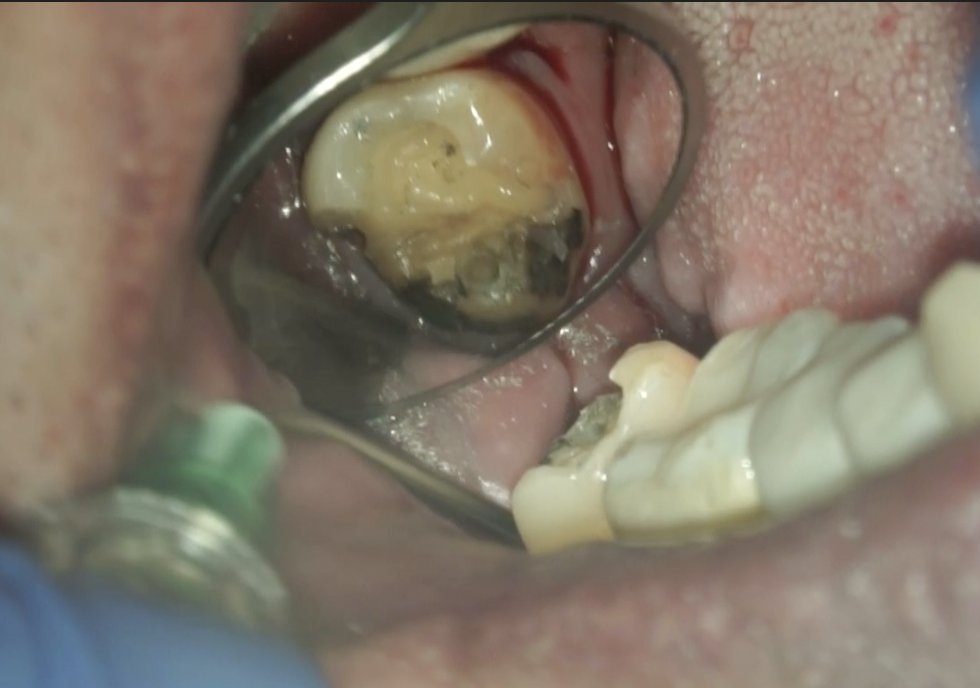

#31 RCT(2026.1.26)

Inlayを除去後に根管治療が始まった。

やはり歯髄炎だ。